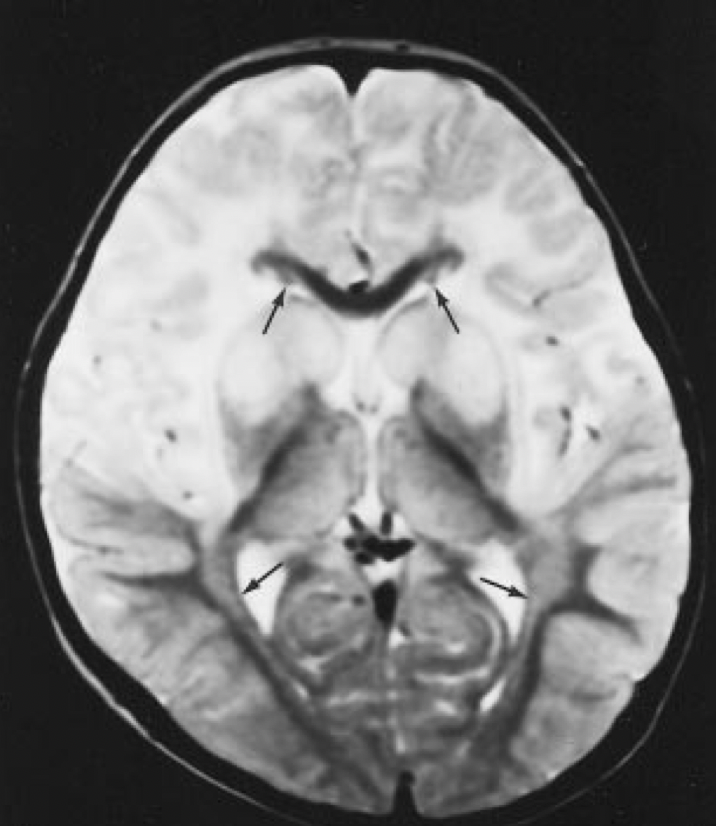

Imagem 2

Intoxicação pelo metotrexate